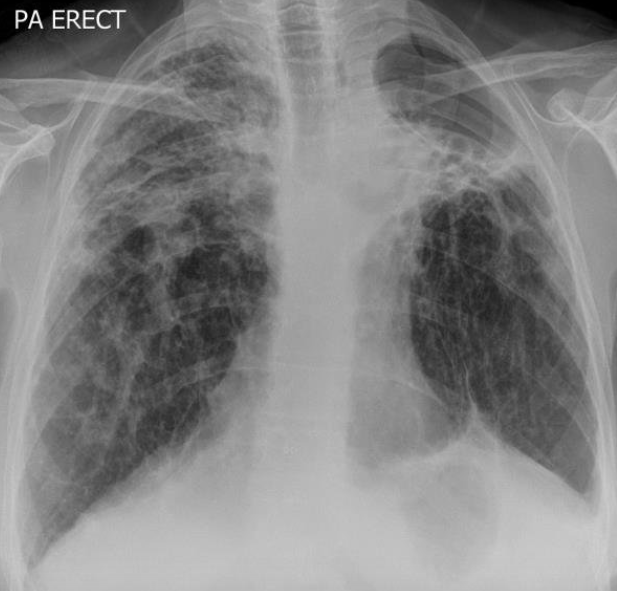

Miliary Nodules

A

1. TB (due to haematogenous spread. 1-3mm micronodules. Immunocom, elderly, children

2. Mets

3. Fungal infection (aspergillus, cryptococcus, histoplasma)

Miliary upper lobe nodules - think inhalational coal workers pneumoconiosis or silicosis